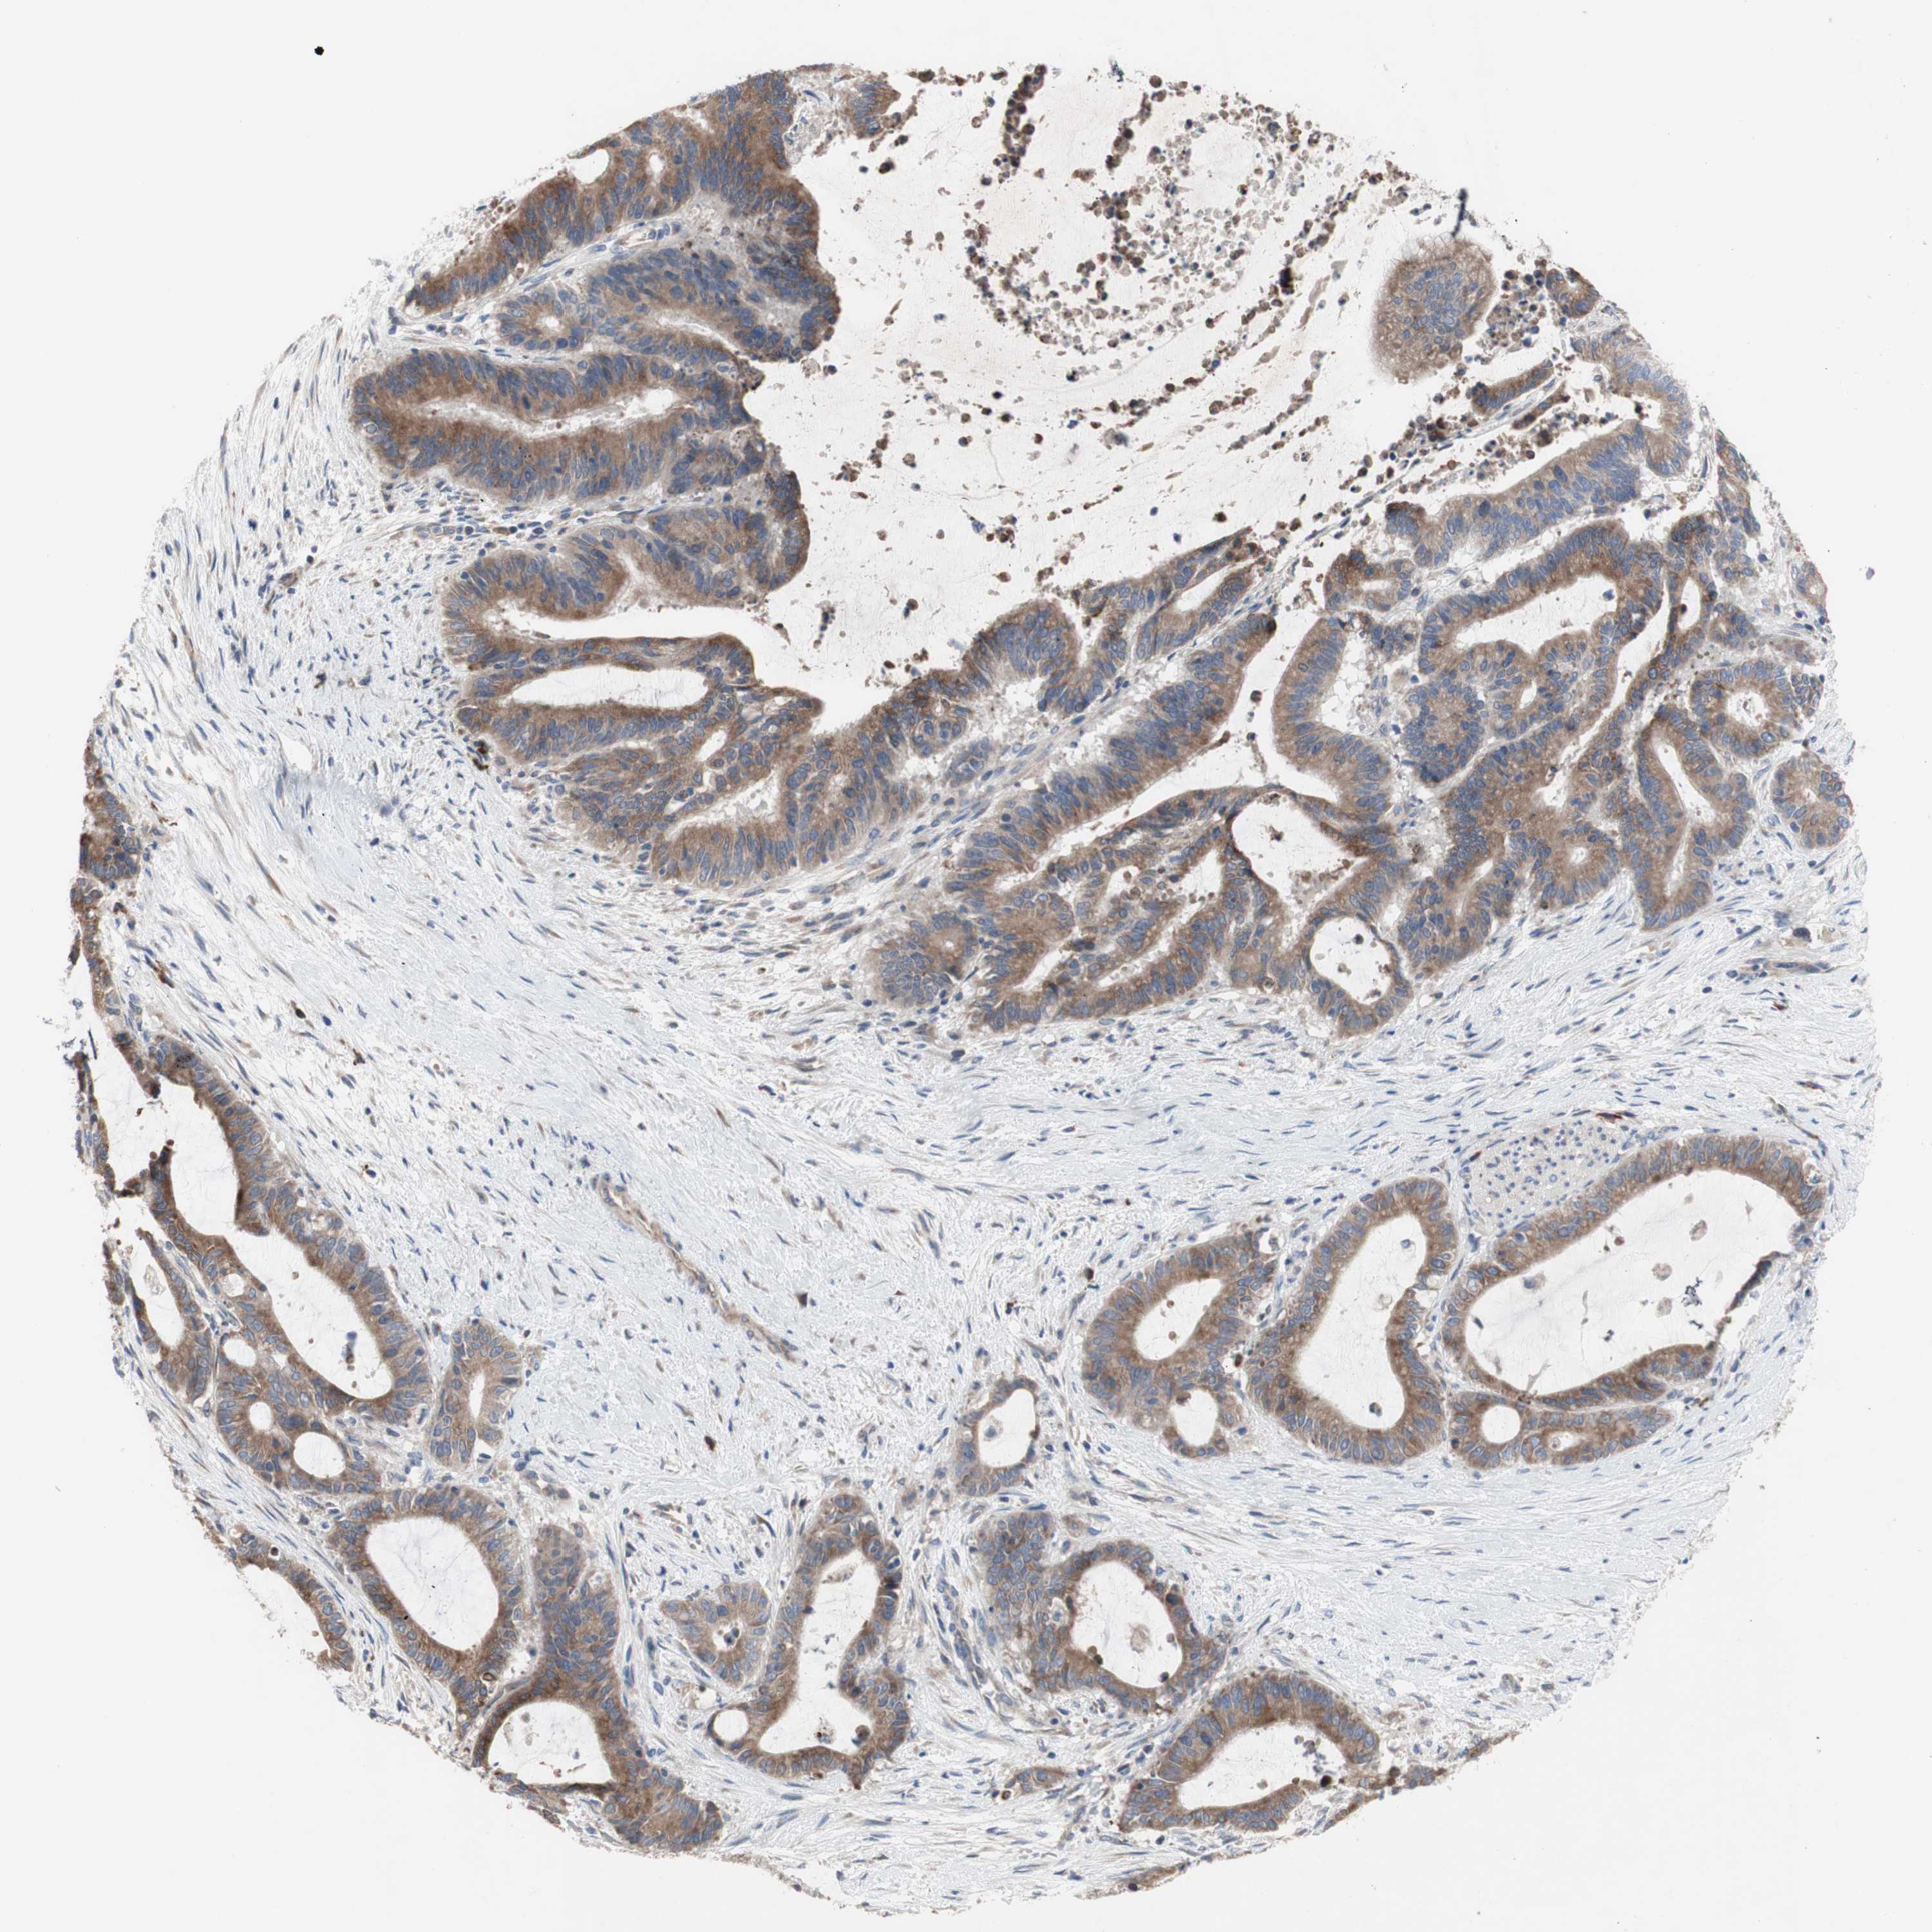

LIVER CANCER - Protein expressioni

A mouse-over function shows sample information and annotation data. Click on an image to view it in a full screen mode. Samples can be filtered based on level of antibody staining by selecting one or several of the following categories: high, medium, low and not detected. The assay and annotation is described here.

Note that samples used for immunohistochemistry by the Human Protein Atlas do not correspond to samples in the TCGA dataset.

Antibody stainingi

Antibody staining in the annotated cell types in the current human tissue is reported as not detected, low, medium, or high, based on conventional immunohistochemistry profiling in selected tissues. This score is based on the combination of the staining intensity and fraction of stained cells.

Each image is clickable and will lead to virtual microscopy that enables deeper exploration of all samples and also displays staining intensity scores, fraction scores and subcellular localization as well as patient and tissue information for each sample.

Antibody HPA009295

Staining

High

Medium

Low

Not detected

Intensity

Strong

Moderate

Weak

Negative

Quantity

>75%

75%-25%

<25%

None

Location

Nuclear

Cytoplasmic/membranous

Cytoplasmic/membranous,nuclear

Cholangiocarcinoma

Carcinoma, Hepatocellular, NOS